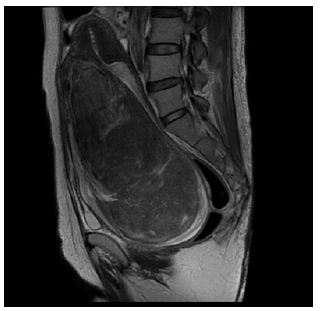

A 53-year-old woman, G2P2 (2 cesarean sections), was referred to us complaining of significant vaginal discharge for 2 years. Pelvic examination detected an over man’s fist sized, well-circumscribed mass in the vagina. Laboratory examinations revealed hemoglobin of 4.5 g/dl. MRI detected a margin-free vaginal mass 8x9x13 cm, with a highly vascular pedicle (Figure 1b). The patient was submitted to transfusion therapy, UAE proceeding later with subsequent total abdominal hysterectomy with salpingo-oophorectomy within 48 hours.

Figure 1b: Large pedunculated submucosal fibroid prolapsed into the vagina in 53-year-old women. Sagittal T2-weighted MR images show a solid mass occupying vaginal cavity (arrow head) and atrophic normalappearing uterus was visible (arrow). Pathologically, the tumor was diagnosed as a leiomyoma.